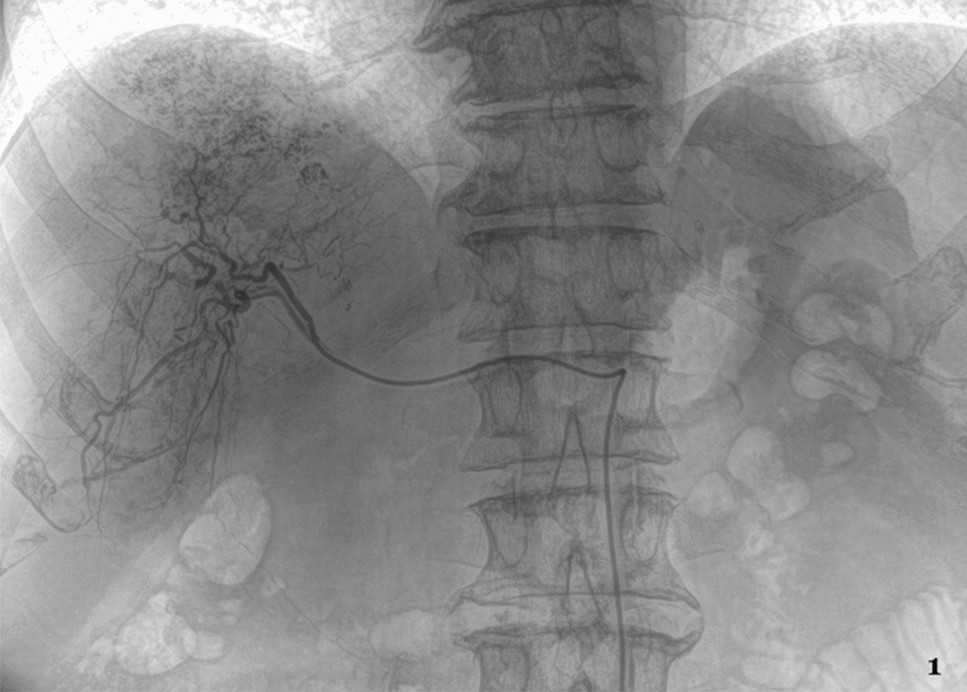

X-ray image. 64 years old male patient with PLC in the RLL during TACE procedure.